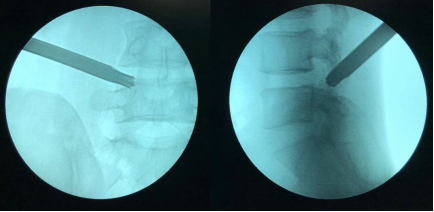

椎间孔镜技术治疗腰椎侧隐窝增生狭窄(320) - 好大夫在线

微创内镜行腰椎侧隐窝狭窄